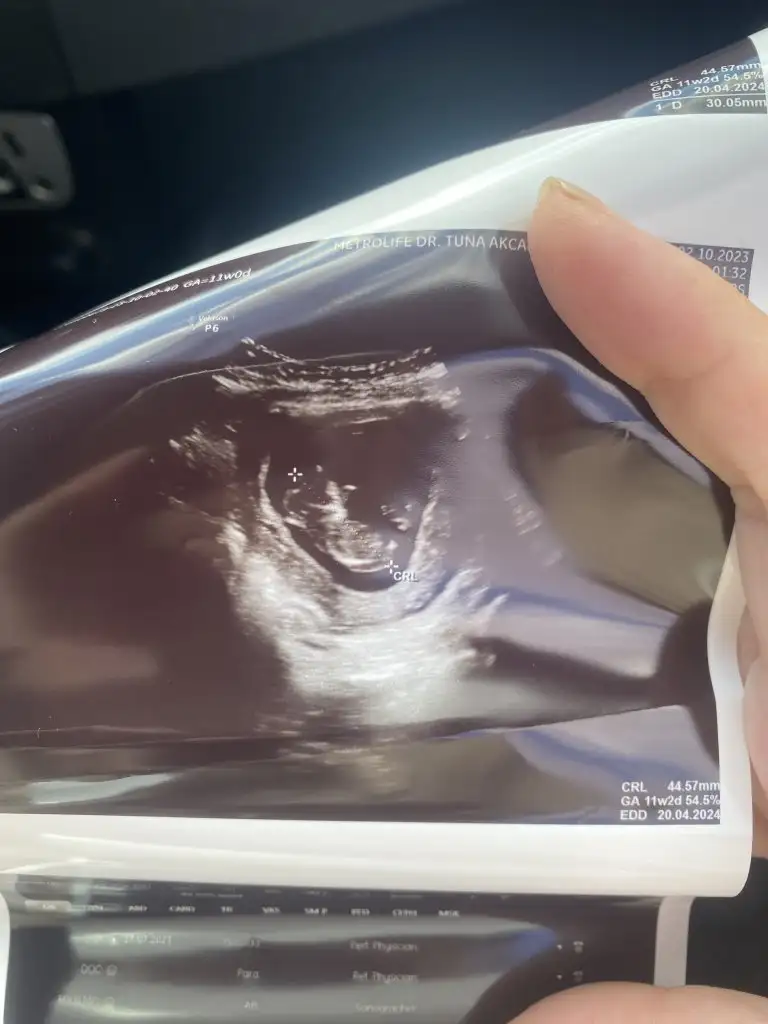

Merhaba arkadaslar , tam 12 haftalıkken doktora gittim 2 li tarama testi için doktor o arada cinsiyet için kemik yapısına göre erkeğe benziyor dedi.Daha sonra kanamam oldu ve daha tecrübeli bir doktora gittim o da laf arasinda %90 kız dedi 12+2 yken dedi ama 2 hafta sonra netleşir dedi. Fakat benim bebeğim geç döllenme olmuştu 6.haftada bebek ve kalp atışı duyulmamıştı 8.haftaya dogru duyulup görülmüştü sizce cinsiyeti ne olabilir kafam karıştı. Sizce geç döllenme olduğu için henüz cinsiyete dair bişey oluşmamış olabilir mi ?Benzer bir durum yaşayan varmı yada 12 haftalikken bişey söylenip değişen varmı?

12. Haftalıkken erkek dediler. 14. hafta kız. Kızım oldu.

Aynısını bende yaşadım ilk erkek dediler ve sonra kız, ondan sonra her ikisi de olabilir bacakları kapalı dendi. Ondan sonra yine kız en son 28 haftalıkken gidince yine kız kesinleşti inşallah 🤲🏼. 29 hafta 2 günlüğüz şu an.